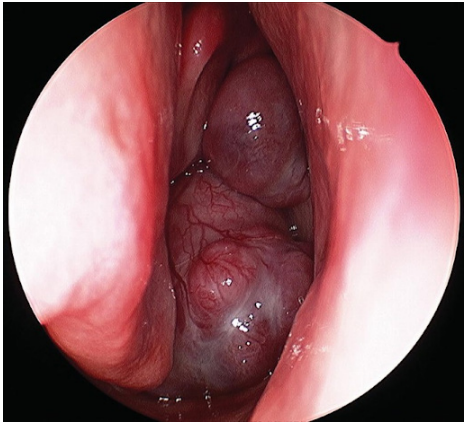

Pólipos nasais: estruturas gelatinosas, vascularizadas, que levam a obstrução nasal e hiposmia importantes em pacientes com polipose intensa. Fonte: https://drjasonroth.com.au/nose-procedures/nasal-polyps/